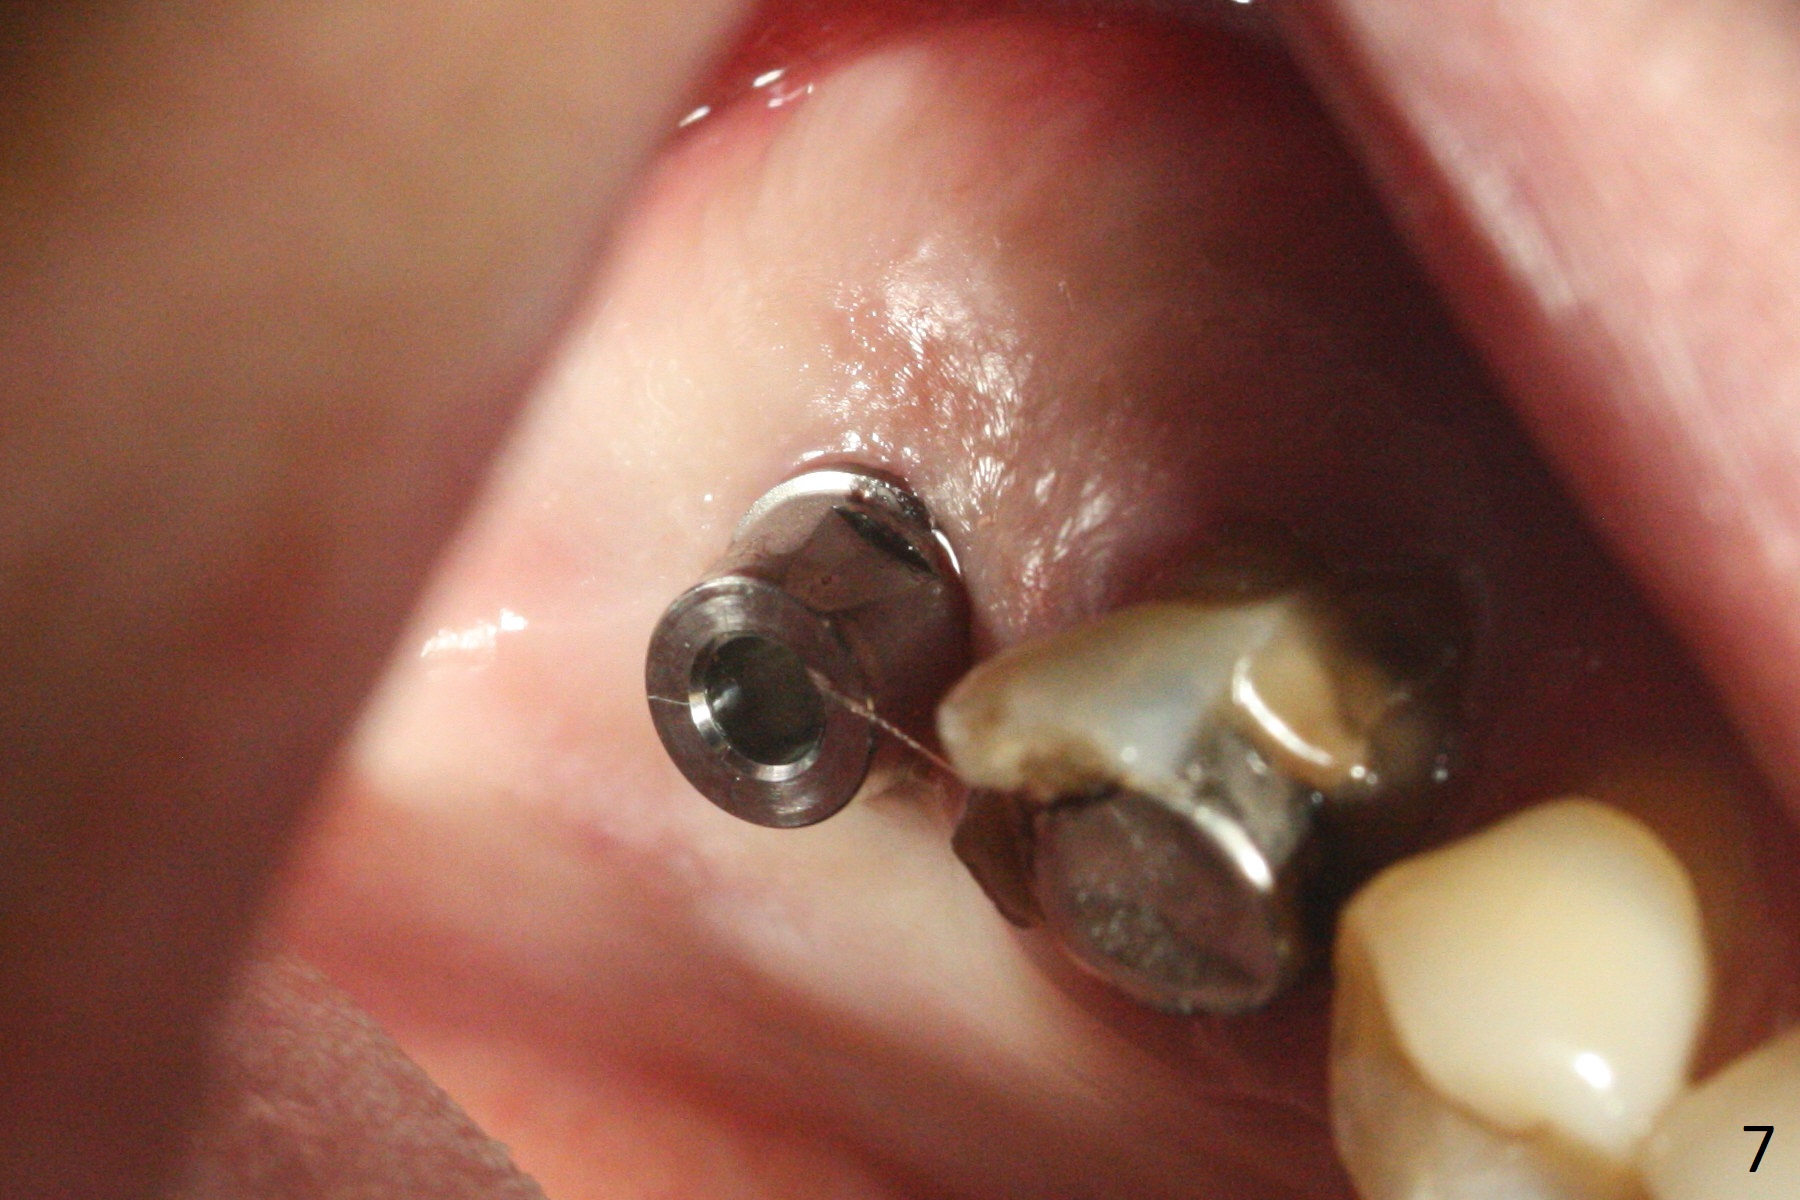

Since the ridge is wide at the site of #2, Magic Split is used for access (flapless) and bone expansion. The bone is so soft that there is no resistance until 4.3 mm Magic Expander is used for 9 mm (Fig.6). A 5 mm tap drill is stable (Fig.1), so are a 5.5x9 mm dummy implant (Fig.2) and a 6x9 mm IBS implant (Fig.3 (<: sinus lift)). In fact the distal thread is still supracrestal (Fig.4 (BW)). After additional 2 mm placement, the distal thread is subcrestal (Fig.5); the mesial margin of a 6.5x4(4) mm abutment is subgingival. A longer cuff (5 mm instead of 4 mm) is more favorable for future restoration. At present the abutment (Fig.7) as well as the tooth #3 with rugged surfaces is used to hold periodontal dressing in place. The abutment margin is completely subgingival 3 months postop (Fig.8 (white dashed line: gingival margin)). It appears that the implant is placed ~ 1 mm deeper than ideal (Fig.9). Diode laser is used for gingivectomy prior to impression. The abutment screw becomes loose 2 months post cementation. After retightening, occlusal equilibrium is conducted with 3 layers of articulating paper. Night guard is provided. The crown/abutment dislodges 1 year 2 months later. Since the gingiva is erythematous, a 6x7 mm healing abutment is placed (Fig.10). The implant seems to have been placed too deep and palatal. It appears that an abutment driver should be buried to prevent the screw re-loosening. Guided surgery should have been done.